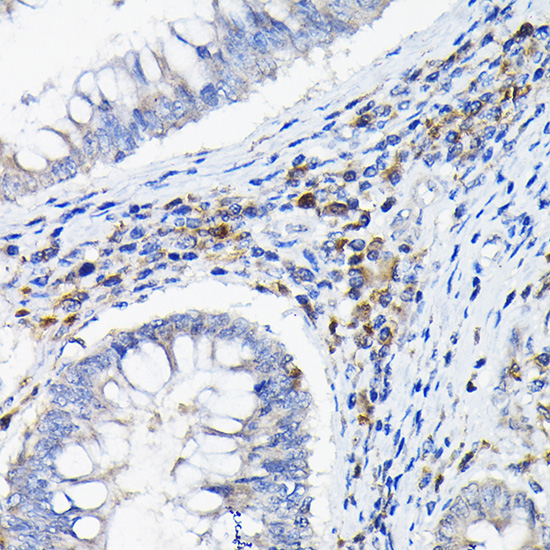

Immunohistochemistry of paraffin-embedded human colon carcinoma using LILRB4 Rabbit pAb.